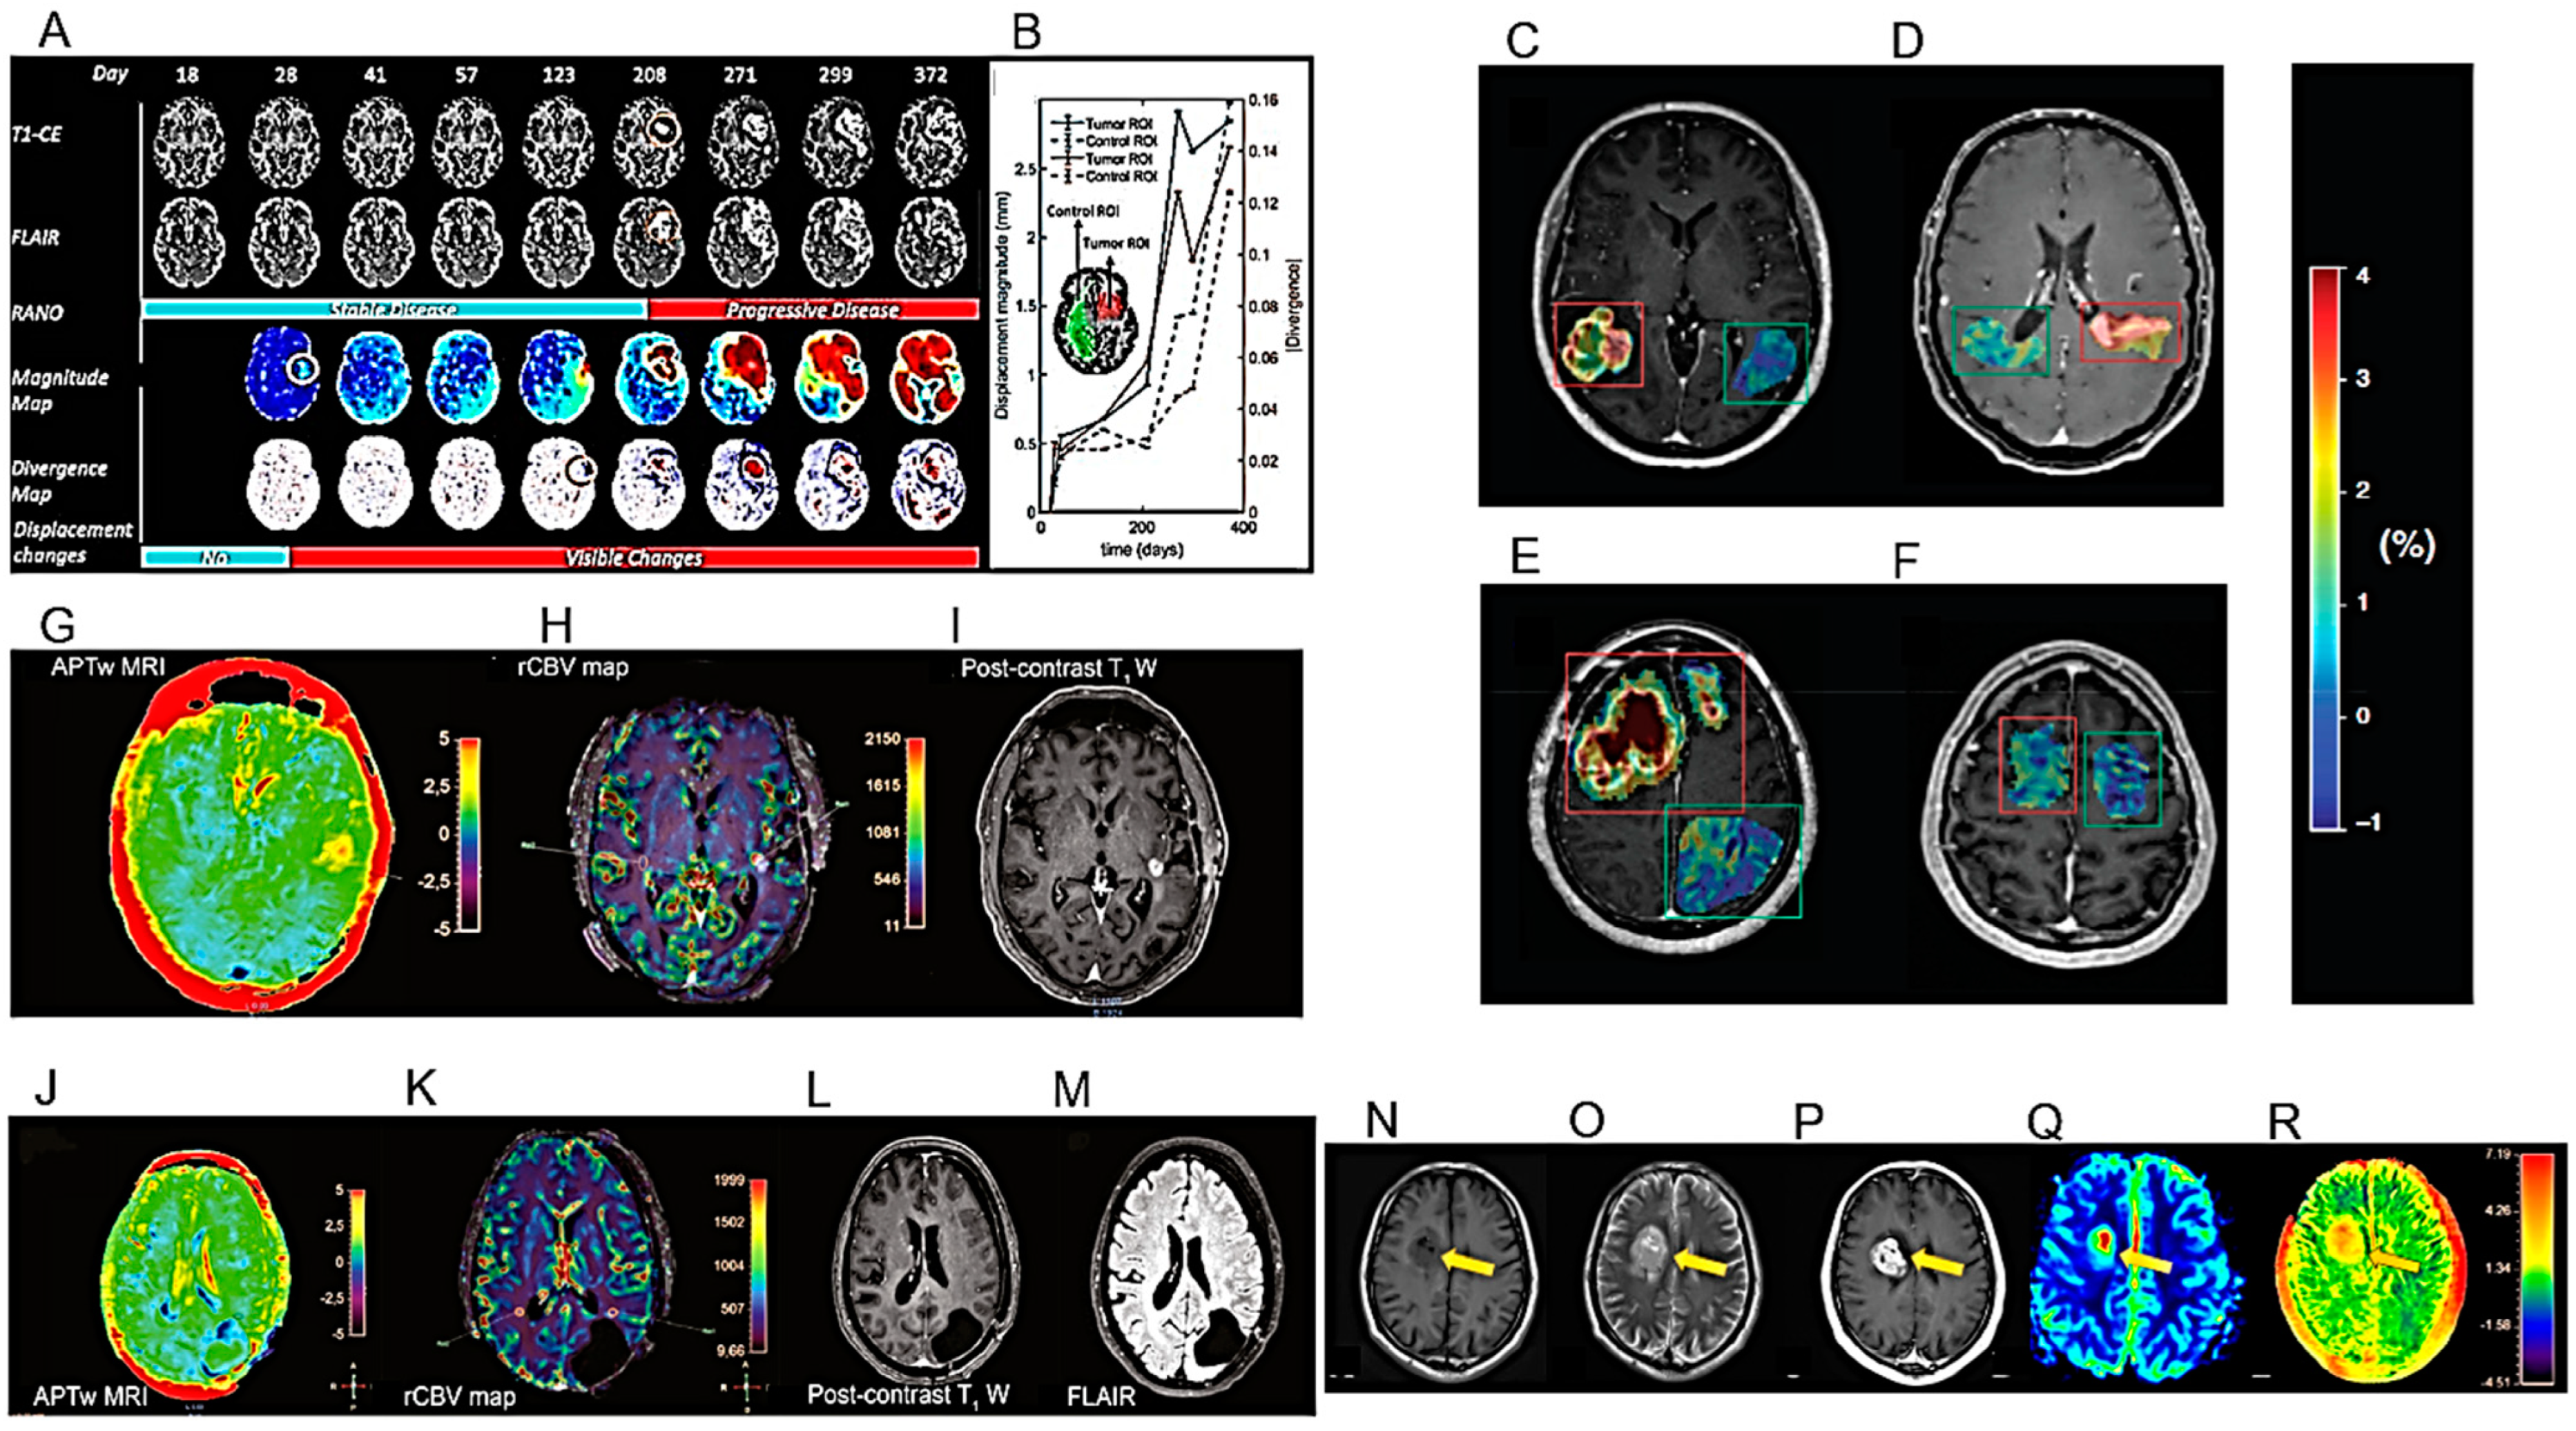

| Proposal of an an automated method to quantify the subtle deformations that occur in the peritumoral regions. | 229 MRI exams from 27 patients with histologically confirmed HGG. | [31] |

| APTw MRI imaging shows good scan–rescan reproducibility in healthy tissue and tumors. | 21 healthy volunteers and 6 glioma patients (4 GBs, 1 oligodendroglioma, 1 radiologically suspected LGG). | [32] |

| APTw MRI max values correlate positively with rCBVmax. | 40 adult patients, treated for histopathologically confirmed glioma (WHO grades II–IV). | [33] |

- Fuster-Garcia, E.; Thokle Hovden, I.; Fløgstad Svensson, S.; Larsson, C.; Vardal, J.; Bjørnerud, A.; Emblem, K.E. Quantification of Tissue Compression Identifies High-Grade Glioma Patients with Reduced Survival. Cancers 2022, 14, 1725. [Google Scholar] [CrossRef]

- Wamelink, I.J.H.G.; Kuijer, J.P.A.; Padrela, B.E.; Zhang, Y.; Barkhof, F.; Mutsaerts, H.J.M.M.; Petr, J.; van de Giessen, E.; Keil, V.C. Reproducibility of 3 T APT-CEST in Healthy Volunteers and Patients with Brain Glioma. J. Magn. Reson. Imaging 2022, 57, 206–215. [Google Scholar] [CrossRef]

- Friismose, A.I.; Markovic, L.; Nguyen, N.; Gerke, O.; Schulz, M.K.; Mussmann, B.R. Amide Proton Transfer-Weighted MRI in the Clinical Setting—Correlation with Dynamic Susceptibility Contrast Perfusion in the Post-Treatment Imaging of Adult Glioma Patients at 3T. Radiography 2022, 28, 95–101. [Google Scholar] [CrossRef]